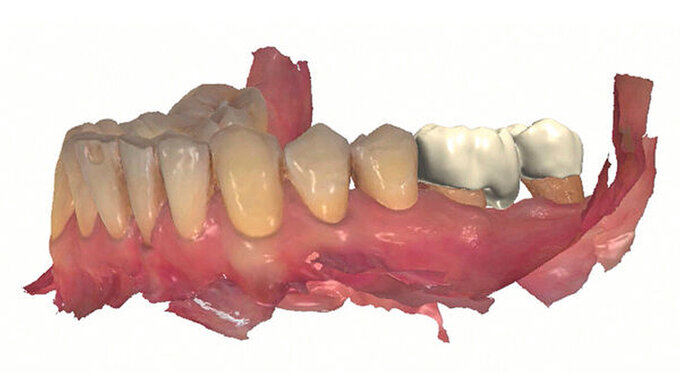

Entsprechend der hier aufgeführten schwachen wissenschaftlichen Evidenz lässt sich schlussfolgern, dass Zähne mit einem Lockerungsgrad II oder höher möglicherweise von einer Schienung vor regenerativen parodontalchirurgischen Eingriffen profitieren können [Cortellini et al., 2001]. Diskutiert wird in diesem Zusammenhang die Förderung der Stabilität des Blutkoagulums durch die Reduktion der Mobilität der Zähne in der Heilungszeit. Nicht zuletzt kann durch eine Schienung das aufgrund der Mobilität mögliche sekundäre okklusale Trauma reduziert beziehungsweise eliminiert werden. In diese Schienungen wird in der Regel jeweils ein benachbarter Zahn ohne erhöhte Mobilität einbezogen. Zwei verschiedene Schienungen zur Reduktion der Mobilität im Rahmen der regenerativen Parodontalchirurgie sind in den Abbildungen 3 und 4 dargestellt.

Während der Anbringung von Schienungen kann die erhöhte Mobilität der Zähne den Schwierigkeitsgrad der Behandlung erhöhen. Es gibt verschiedene Möglichkeiten, die Zähne in der gewünschten Position zu fixieren und somit die Zähne in der richtigen Position schienen zu können. Eine Möglichkeit der Fixierung besteht im temporären Anbringen von Komposit ohne adhäsive Verankerung auf der gegenüberliegenden Seite der Zähne, an der die Schienung angebracht werden soll [Kumbuloglu et al., 2011]. Nach Anbringen der Schienung kann das nicht-adhäsiv verankerte Komposit restlos entfernt werden. Eine zweite Möglichkeit besteht in der Herstellung von zahntechnisch hergestellten, abnehmbaren Widerlagern aus einem Kompositmaterial für die zu schienenden Zähne, die zuvor in der gewünschten Position gescannt wurden. Optische Abformungen weisen im Gegensatz zu klassischen Abformungstechniken mit Abformmassen in der Regel kein Risiko für eine Stellungsänderung der mobilen Zähne auf. Diese Widerlager halten die Zähne während der Anbringung der Schienung in der gewünschten Position [Liu et al., 2023].